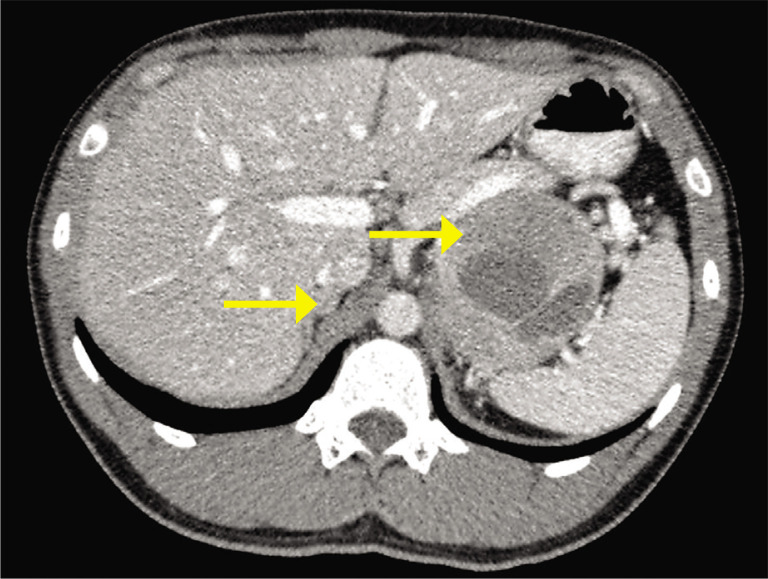

嗜铬细胞瘤和副神经节瘤综合征根据其潜在的遗传改变分为三种特定的疾病群。影响髓细胞瘤病相关因子X (MAX)基因的致病变异易使嗜铬细胞瘤和副神经节瘤综合征发生在更年轻的年龄,其中一半以上患有双侧嗜铬细胞瘤。我们报告一例双侧嗜铬细胞瘤,在MAX基因(c.234_235dup)中发现了一种新的致病变异。这位年轻的男性在表现出严重的高血压和心肌梗塞后被发现有一个巨大的左肾上腺上肿块。他的内分泌检查证实了嗜铬细胞瘤的诊断,尿中去甲肾上腺素、肾上腺素和3-甲氧基酪胺水平升高。肾上腺CT示双侧肾上腺肿物;左侧肾上腺肿块最宽直径约为8cm,右侧肾上腺肿块最宽直径约为2cm。68镓- dotatate功能成像显示左侧肾上腺肿块明显摄取,但右侧不确定,其他地方未见明显摄取提示转移灶。他没有多发性内分泌瘤、神经纤维瘤病或von Hippel Lindau病相关的综合征特征。这些共同的发现提出了是否应该进行单侧或双侧肾上腺切除术的临床困境。因此,致病MAX基因的检测对于指导个性化治疗策略至关重要。在双侧肾上腺切除术后,他的高血压被治愈了。根据国际共识,计划每年进行一次生化筛查和每两年进行一次MRI检查以寻找嗜铬细胞瘤的复发。

Pheochromocytomas and paragangliomas syndrome are grouped into three specific disease clusters based on their underlying genetic alterations. Pathogenic variants affecting the myelocytomatosis-associated factor X (MAX) gene predispose pheochromocytomas and paragangliomas syndrome to occur at younger ages, with more than half having bilateral pheochromocytomas. We report a case of bilateral pheochromocytomas with a novel pathogenic variant identified in the MAX gene (c.234_235dup). This young male was found to have a huge left suprarenal mass after he presented with severe hypertension and myocardial infarction. His endocrine workup confirmed a diagnosis of pheochromocytoma as evidenced by elevated levels of normetanephrine, metanephrine, and 3-methoxytyramine in the urine. CT of the adrenal glands revealed bilateral adrenal masses; the widest diameter for the left adrenal mass was almost 8 cm whereas for the right one was 2 cm. 68Gallium-DOTATATE functional imaging showed significant uptake in the left adrenal mass, but indeterminate on the right, and no significant uptake was seen elsewhere to suggest metastatic lesions. He did not have syndromic features associated with multiple endocrine neoplasia, neurofibromatosis or von Hippel Lindau disease. The collective findings raised the clinical dilemma of whether unilateral or bilateral adrenalectomy should be pursued. The detection of pathogenic MAX gene was therefore crucial in guiding personalized treatment strategy. Following the bilateral adrenalectomy, his hypertension was cured. Annual biochemical screening and 2-yearly MRI imaging to look for recurrence of pheochromocytomas were planned according to international consensus.